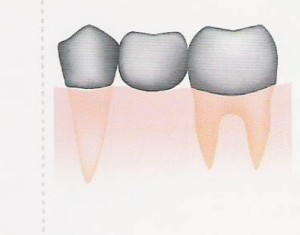

■ ブリッジ |

1)材料によっては保険でも治療できます。異物感は比較的少ないです。 2)両隣の歯を削って支える為、支えの歯が弱り、歯の寿命を短くします。 3)保険のブリッジの場合には、見栄えが悪いことがあります。